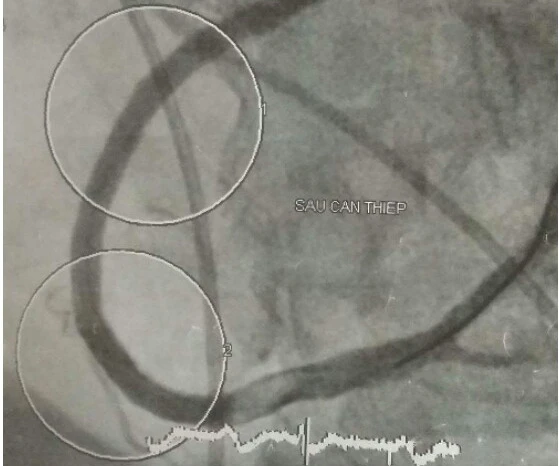

Tuy nhiên, một tình huống mới xảy ra. Sau khi ông K. qua khỏi cơn rung thất thì nhịp tim lại quá chậm, không đủ đảm bảo chức năng sống. Các BS nhanh chóng đặt ống nội khí quản để đảm bảo chức năng hô hấp và đặt máy tạo nhịp tạm thời để có thể nhanh chóng can thiệp nhánh động mạch vành bị tắc. Được sự hỗ trợ chuyên môn của các BS ở Viện Tim TP.HCM, mạch máu bị tắc của bệnh nhân đã thông trở lại.